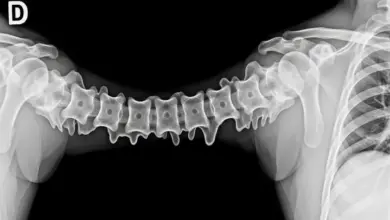

A escoliose lombar de convexidade esquerda é uma condição caracterizada por um desvio lateral anormal da coluna vertebral na região lombar, onde a curvatura se projeta para o lado esquerdo.

Quando observada de costas, nota-se que a coluna forma um “C” ou “S” com a parte convexa voltada para o lado esquerdo na região lombar.

Radiografias são instrumentos essenciais para visualizar o grau de curvatura e identificar se há uma necessidade iminente de correção escoliose lombar.

Por fim, o ângulo de Cobb é uma medida padrão utilizada para quantificar a severidade da escoliose, e dependendo do tamanho deste ângulo, o tratamento pode abranger desde práticas conservadoras até abordagens mais invasivas.